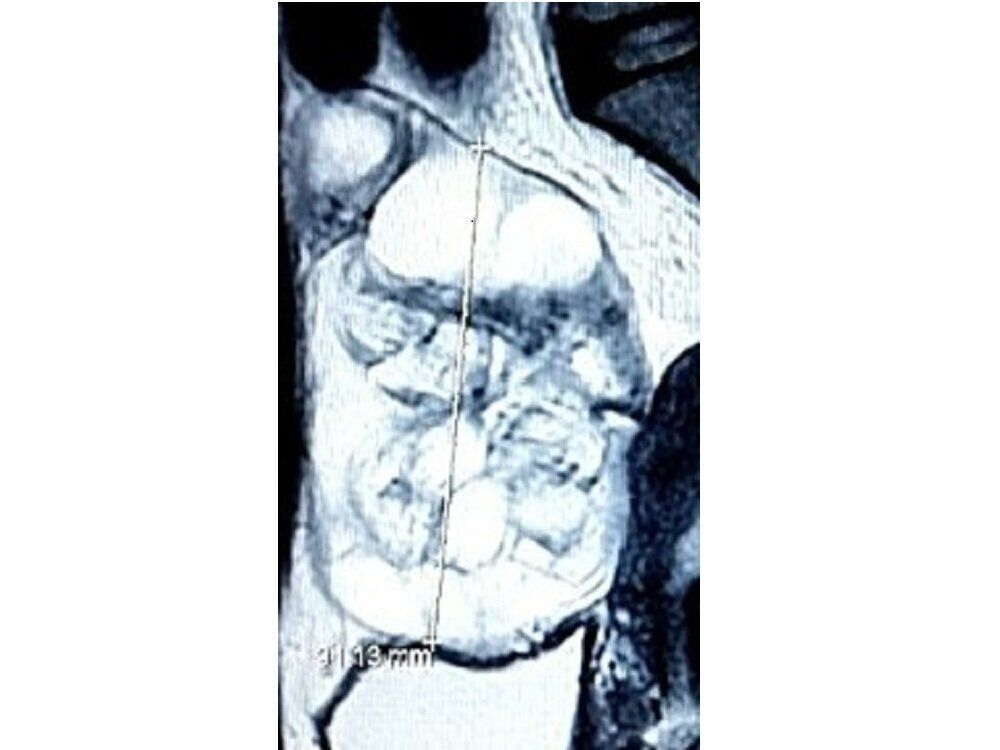

エコー検査をしたところ「腹水がたまっているから、紹介状を書きます」と言われ、その足で紹介された総合病院の婦人科に行き、CT検査をしました。画像を見ると、右の卵巣が大きく腫れあがりボコボコしていたんです。右の卵巣は、わずか1年で9センチも大きくなっていました。痛みも治まらないので、そのまま入院しました。

医師からは最初「卵巣境界悪性腫瘍(らんそうきょうかいあくせいしゅよう)だろう」と言われました。卵巣境界悪性腫瘍とは、良性・悪性の明確な判断が難しく、中間に位置づけられる腫瘍です。しかし画像を見た医師は、「たぶん、悪性だと思う」と言いました。